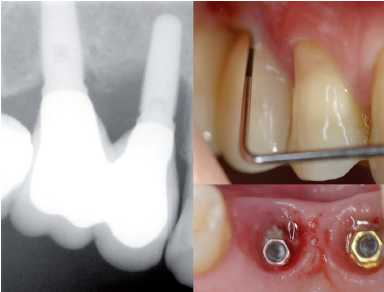

— Exploración radiológica al cumplirse un año

desde el último control radiológico.

• Rx. Periapicales en aquellos implantes comprometidos: espiras

expuestas, movilidad, sangrado, etc., con técnica de

paralelización.Esta técnica nos asegura que la

proyección es la misma y evita distorsiones que pueden

llevar al clínico a una lectura distinta a la situación

real de pérdida ósea o desajuste de la conexión

del implante con la prótesis (Figura 7).